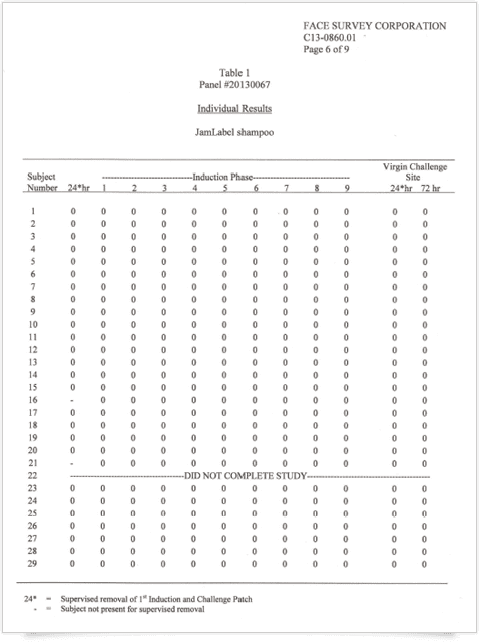

刺激反応なしを表す オールゼロの検証結果